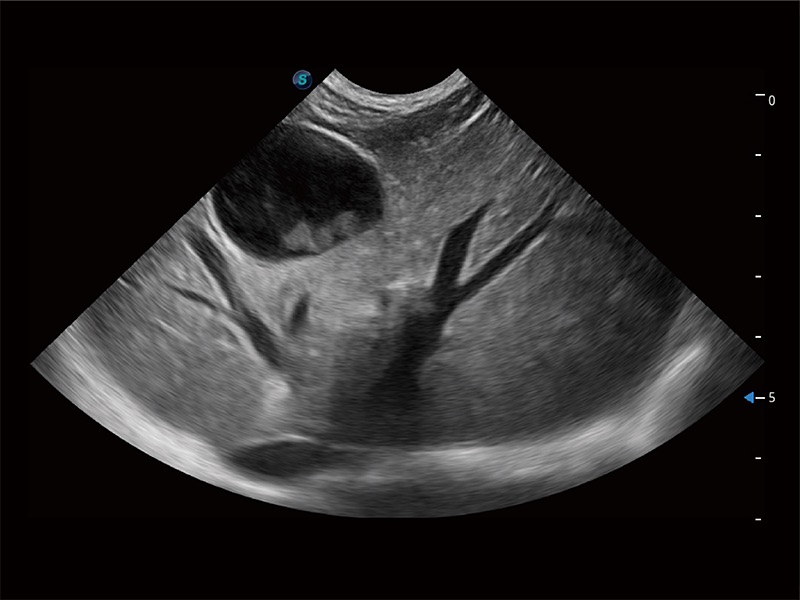

高性能和先进的临床应用工具可以为动物医生提供临床信心。ProPet 80 搭载了先进的腹部和浅表应用工具,帮助医生在日常临床实践中发挥前所未有的作用。

极大提升超低速微细血流的检出能力,同时更精准地滤除软组织和超声信号,为兽用医生提供以往无法通过常规血流获得的疾病诊断信息。

操作简便,无需高频度外力作用即可真实反映组织的形变,快速评估肿瘤良恶性。